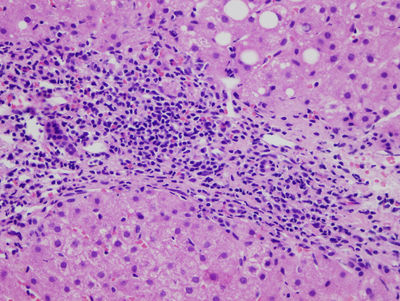

29. Hombre ADVP de 32 años de edad que acude a urgencias por fractura de peroné. La exploración física general rutinaria muestra hepatomegalia. La analítica muestra una ligera disminución de las proteinas totales y la albúmina con un incremento de los valores de ALT y AST. Los anticuerpos séricos anti-VHC son pósitivos así como los los antiVHBs. Tras el tratamiento de su fractura se le realiza biopsia hepática percutánea que se muestra en la imagen. ¿Cuál es el diagnóstico más probable?

Select one of the following: